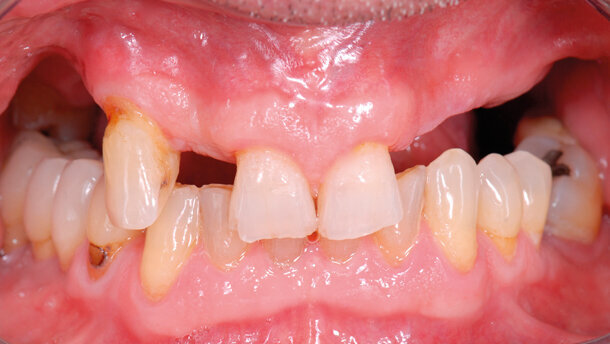

Nel caso raffigurato il paziente portatore di una protesi scheletrata nell’arcata superiore chiede una riabilitazione fissa del mascellare superiore (Figg. 1-5).

L’anamnesi positiva per una sinusite cronica e un’abitudine viziata di forte fumatore ha escluso l’intervento di elevazione della membrana sinusale.

L’alternativa chirurgica adottata prevede il posizionamento di impianti inclinati mesiali alla parete anteriore del seno con emergenza protesica in corrispondenza del primo molare per permettere una riabilitazione senza cantilever distali, sia nel primo che nel secondo quadrante.